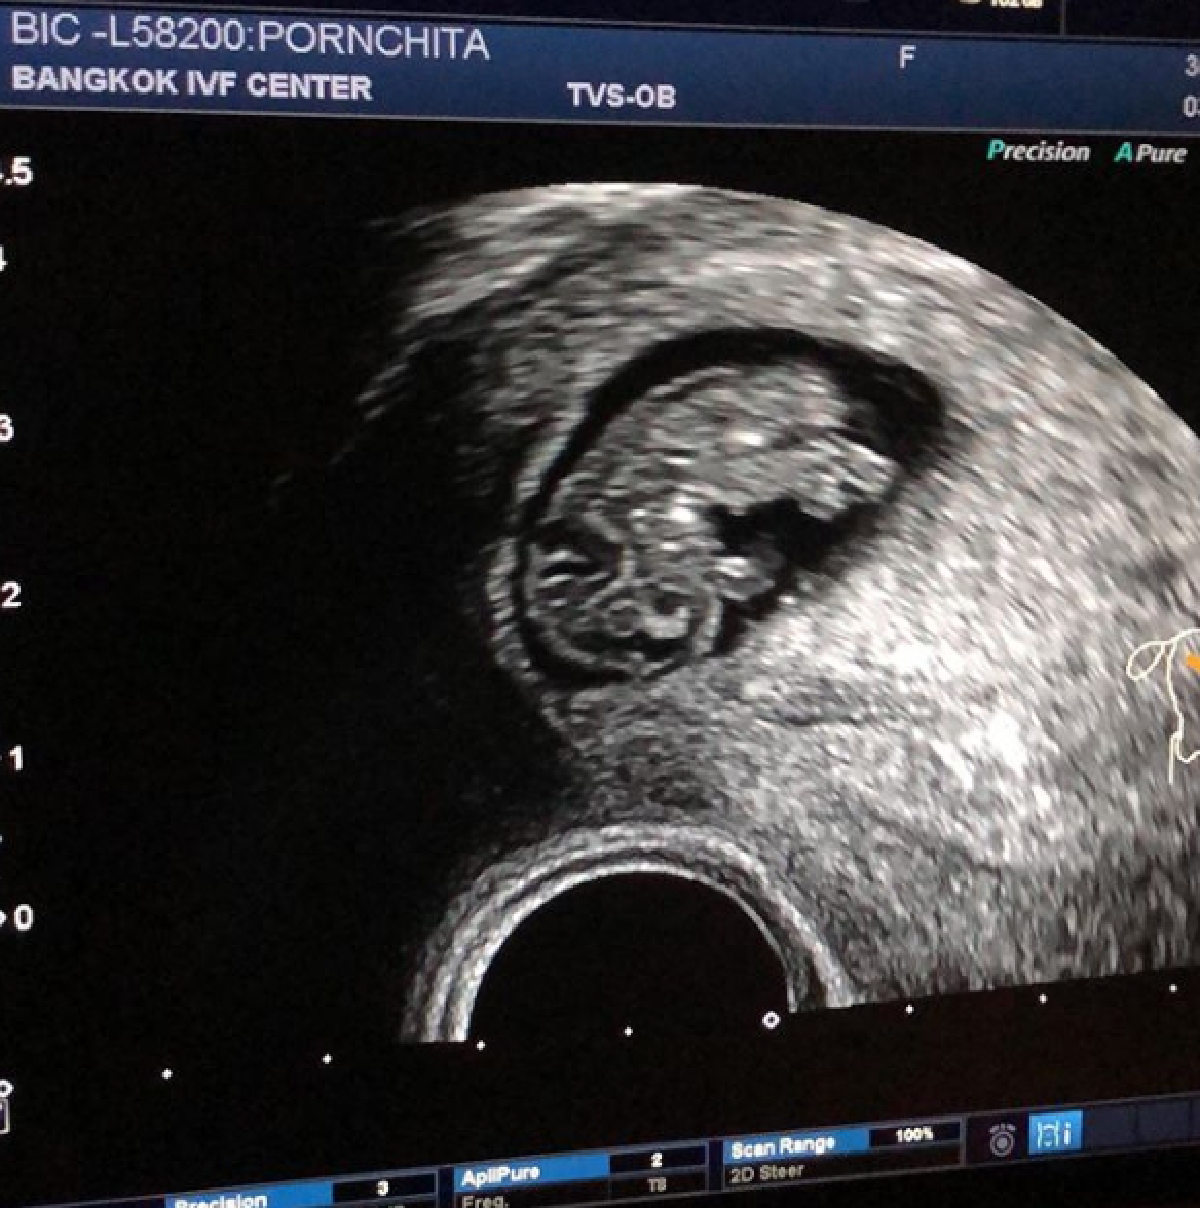

โดย ทั้งคู่ ได้เผยภาพอัลตร้าซาวด์ พร้อมบอกเพศได้ ลูกชาย สมใจพ่อมิคสักที ทั้งนี้ต้องตั้งชื่อตัว ปอ ปลา นำหน้าให้เข้ากับพี่ๆทั้งสองอีกต่างหาก งานนี้ น้องปริม ได้ตั้งชื่อให้น้องแล้วว่า ปุ้ย จะเก็บไว้เรียกคนเดียว